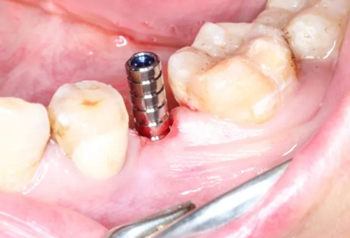

3、手術(shù)過程

1.碘伏浸泡消毒后的導(dǎo)板在患者口內(nèi)試戴,就位準(zhǔn)確、十分穩(wěn)固。

2.使用牙齦環(huán)切刀施行不翻瓣手術(shù),創(chuàng)傷小,保護(hù)患者牙齦軟組織形態(tài)。

3.根據(jù)手術(shù)計(jì)劃書,使用術(shù)前所設(shè)計(jì)好的長度、直徑的一系列鉆針在導(dǎo)板的引導(dǎo)下進(jìn)行備孔。

4.在全程導(dǎo)板的引導(dǎo)下,使用全程導(dǎo)板工具盒中的攜帶器,從導(dǎo)板套環(huán)孔處將植體植入,直至攜帶器的六角、與導(dǎo)板套環(huán)的六角嚴(yán)絲合縫(如圖,六角對(duì)六角),即表示植體就位成功。